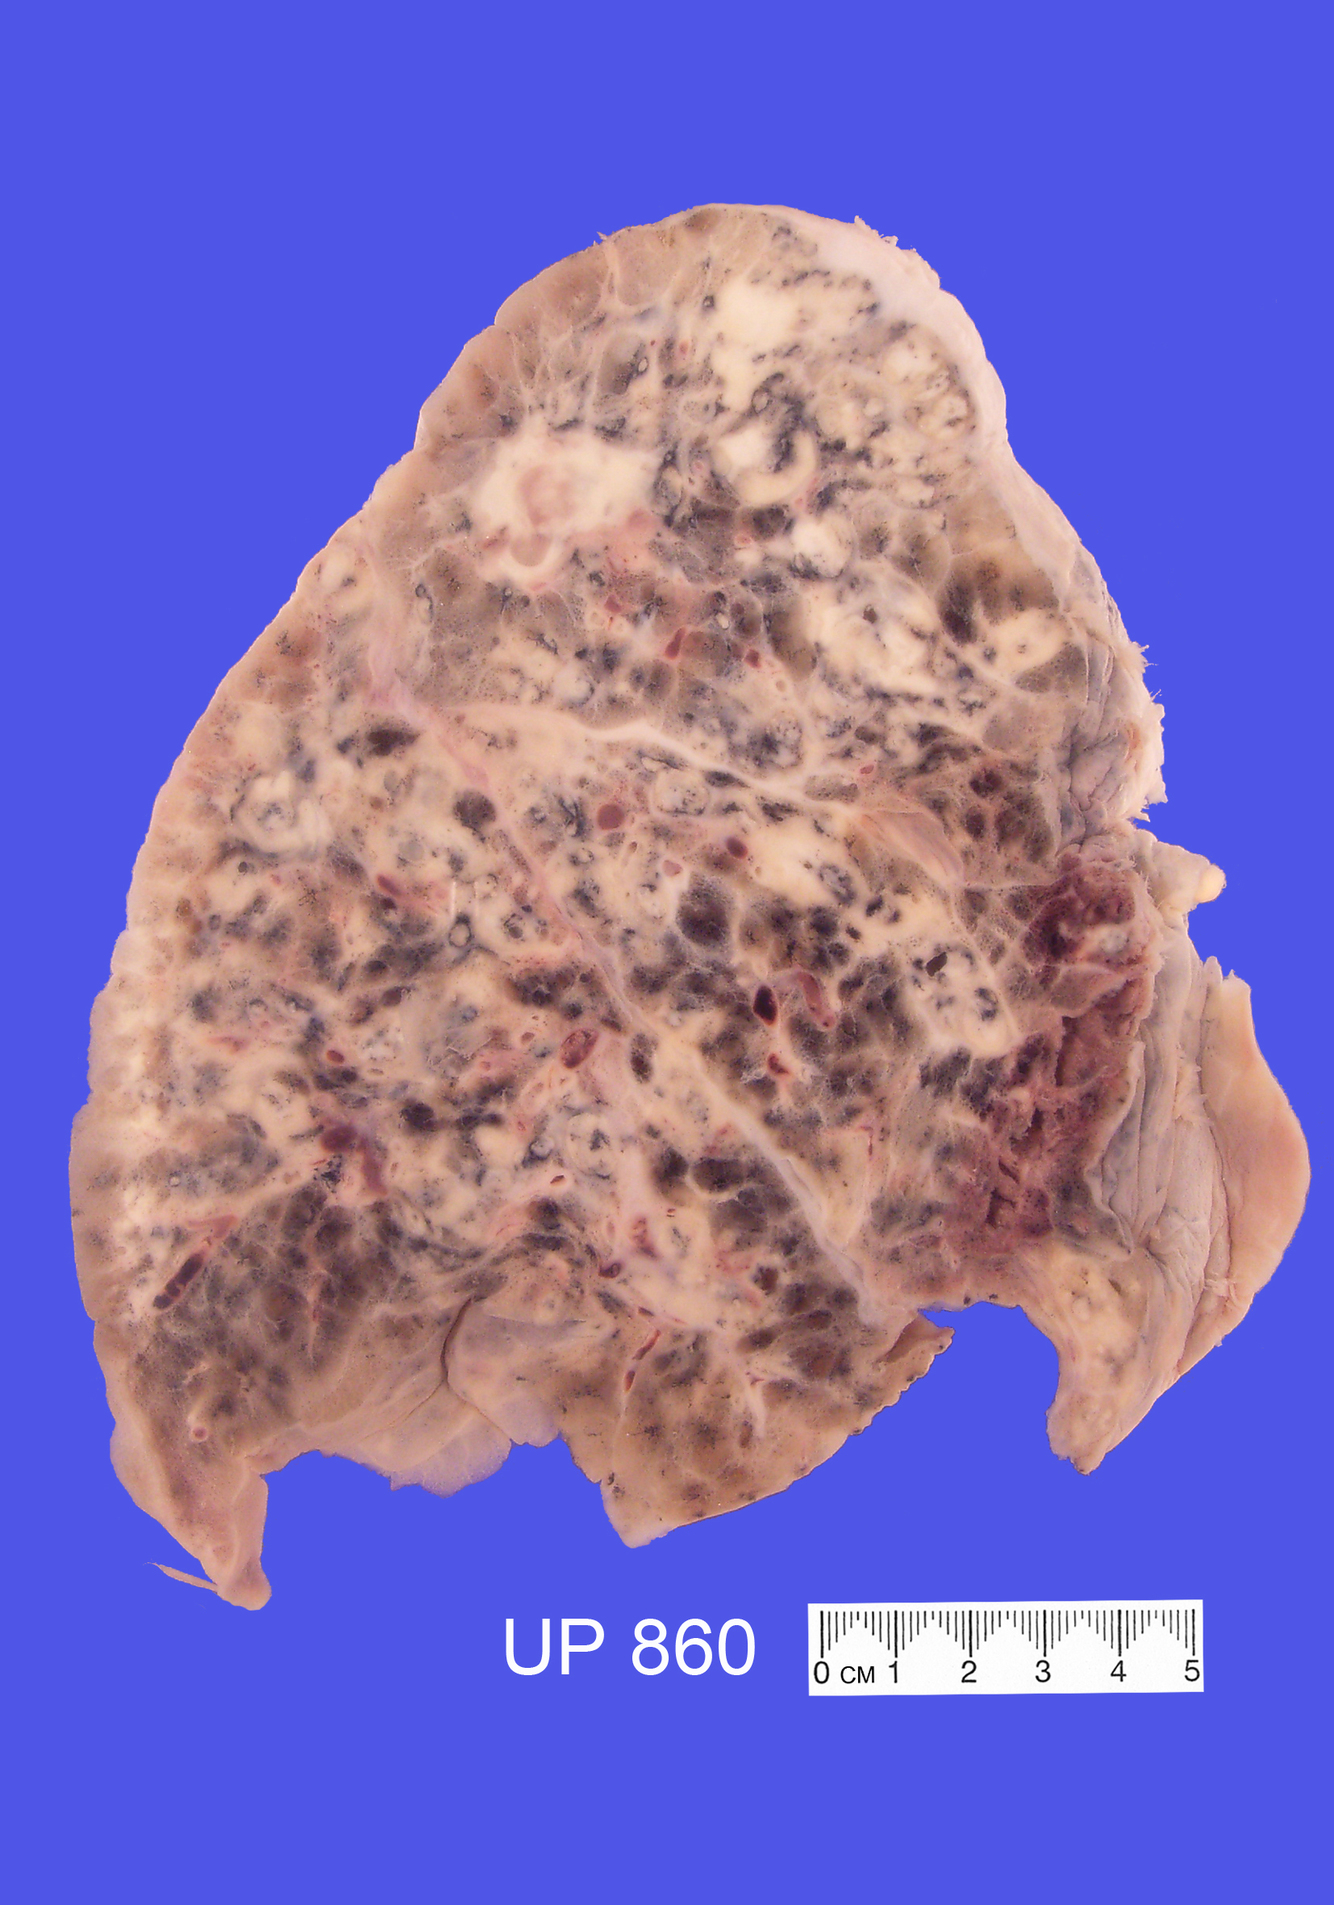

Describe

The specimen is a slice through the Right Lung

Diffuse consolidation, suppuration and necrosis is seen throughout all three lobes, with some sparing of parenchyma towards the inferior aspect of the lower lobe

There are multiple creamy yellow, variably sized foci

the largest of which shows cavitation - abscess formation

This is evident of beonchopneumonia with an abscess

The parts of the lung unaffected by the bronchopneumonia appear emphysematous

There is an apical scar which may be from old TB